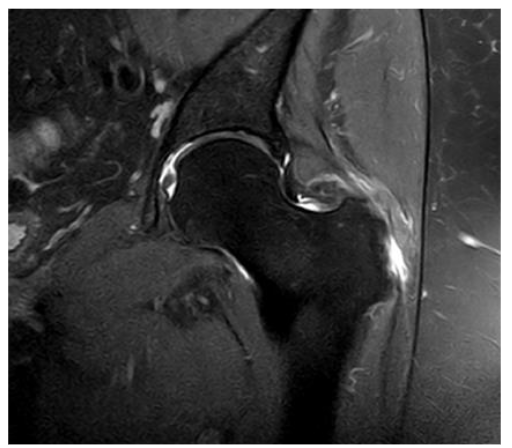

Figure 7. Hip MRI scan showing a 30% rupture of the gluteus medius and minor tendons